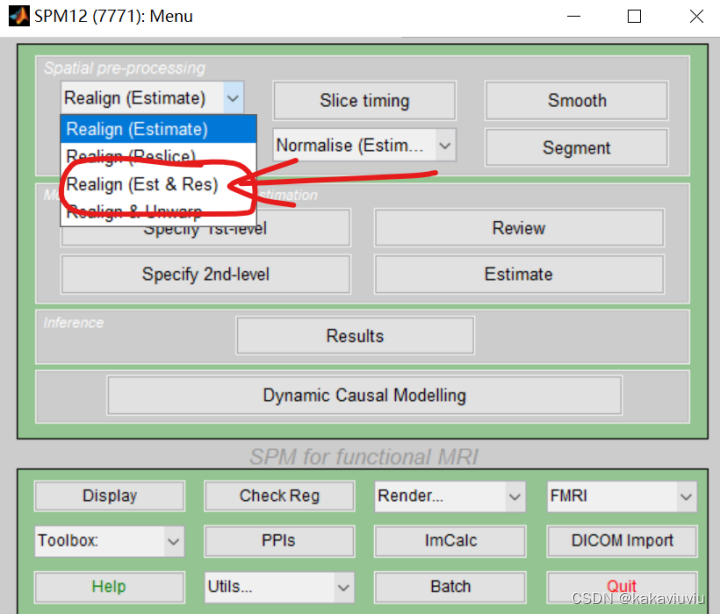

(3)R:realign 头动校正

双击

只筛选以a为开头的文件(上一步生成的时间校正后的文件)

文件选中就可以运行了。Num passes 后面的register to mean:选中to fist 与第一张图象对齐,to mean,就是与平均的对齐